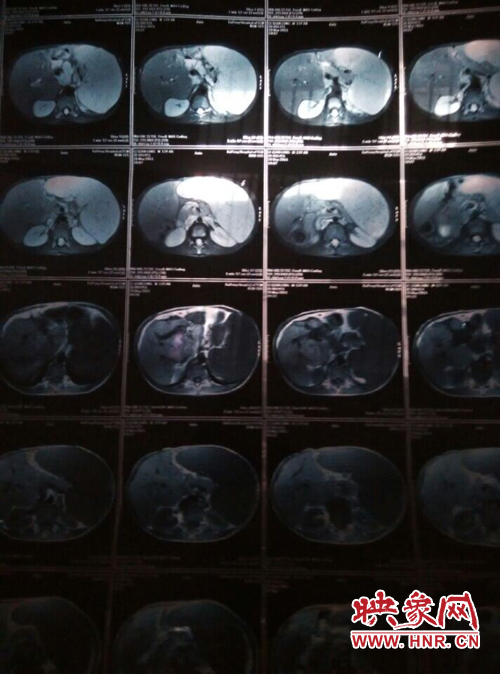

映象網(wǎng)商丘訊(記者 曾巖 代艷)他是一個(gè)花季少年,兩歲半時(shí)患上怪病,經(jīng)過(guò)漫長(zhǎng)的求醫(yī)之路查出是肝脾腫大,十幾年的看病之路,花了幾十萬(wàn),非但沒(méi)有醫(yī)好他的病,讓這個(gè)原本就貧困的家庭雪上加霜。

他叫李乾龍,今年16歲,家住寧陵縣城郊鄉(xiāng)李莊村,家里有四口人,目前在寧陵縣黨校就讀上高一,他一邊上學(xué)一邊看病,十幾年來(lái),他們跑遍了大小醫(yī)院,卻一直沒(méi)查出他的病因。16歲的他發(fā)育的還沒(méi)有13歲的弟弟高,肚子大的像個(gè)皮球,經(jīng)常身體發(fā)熱,全身無(wú)力,因?yàn)闆](méi)錢(qián)去大醫(yī)院檢查治療只得在家保守治療。